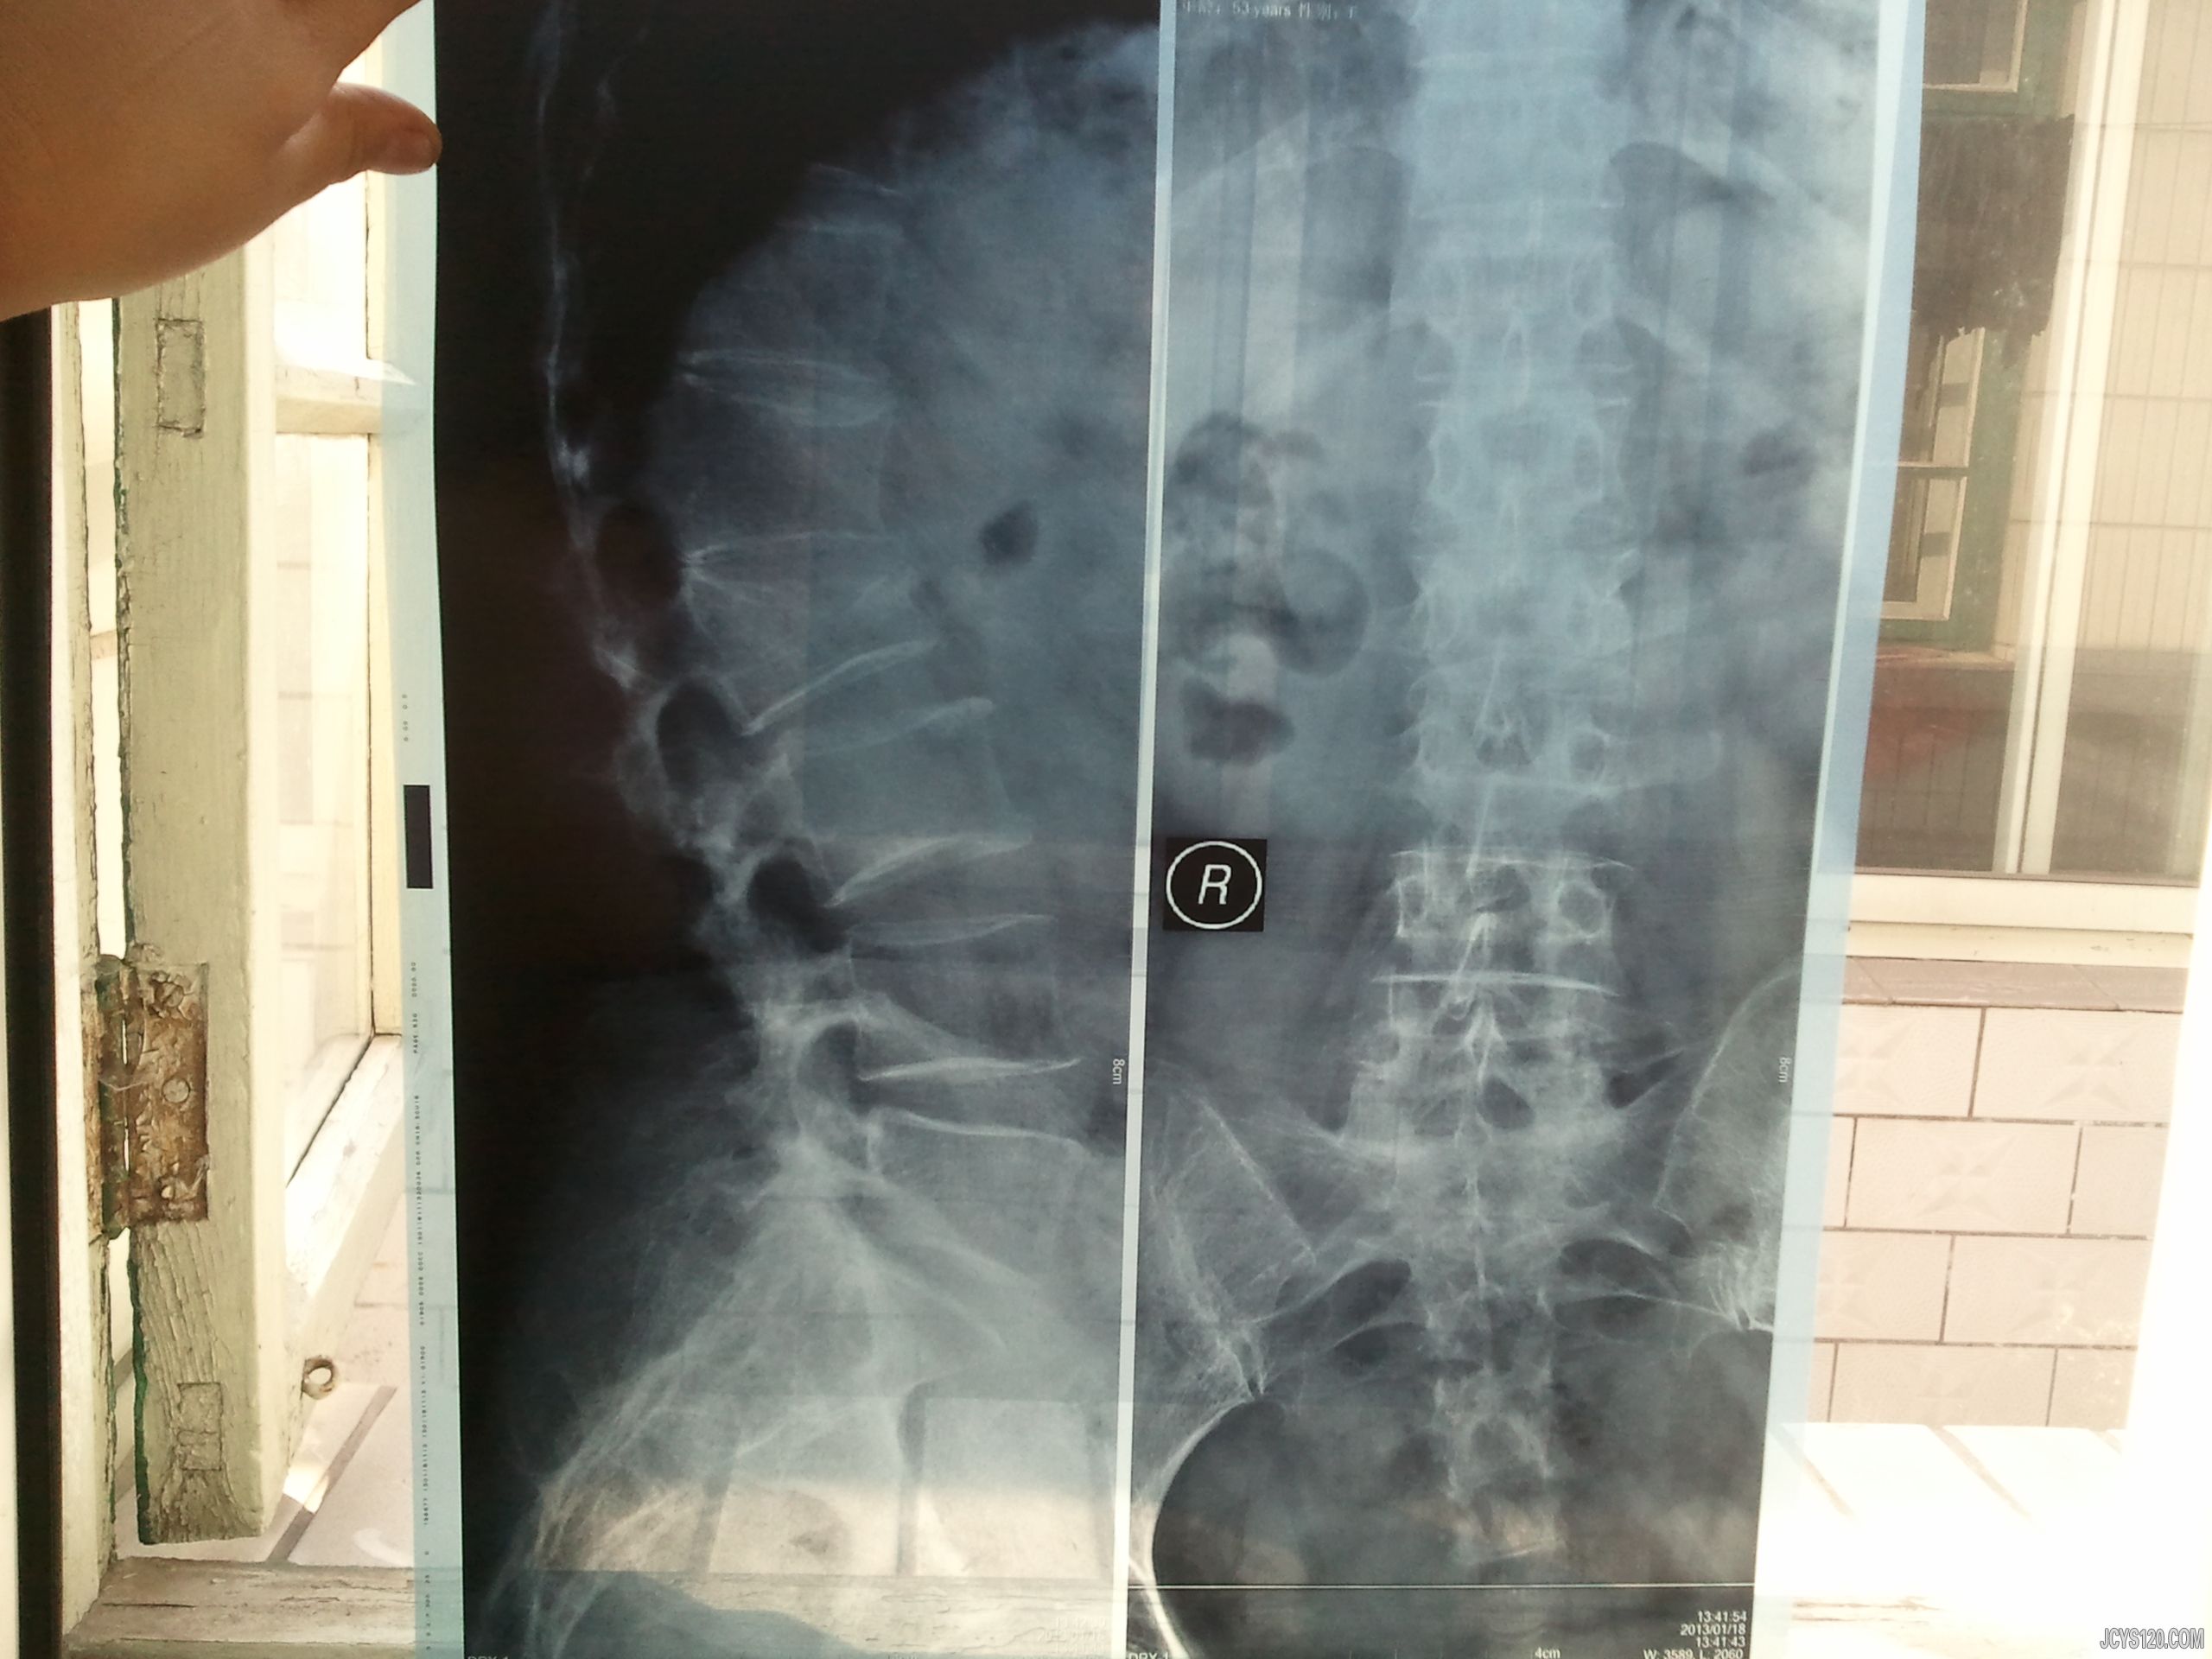

• 腰扭伤 attach_img

• 西礼尚庄 2013-3-4

• 患者50岁左右,女,半年前腰部扭伤,通过休息静养,腰部疼痛的症状明显好转,3个月前再次过度运动腰部扭伤,随去医院就诊,拍片如下,二院大夫让他静养,可现在依然腰痛,尤其翻身时像针刺一样,请各位老师给予指点 ...  阅读全文>